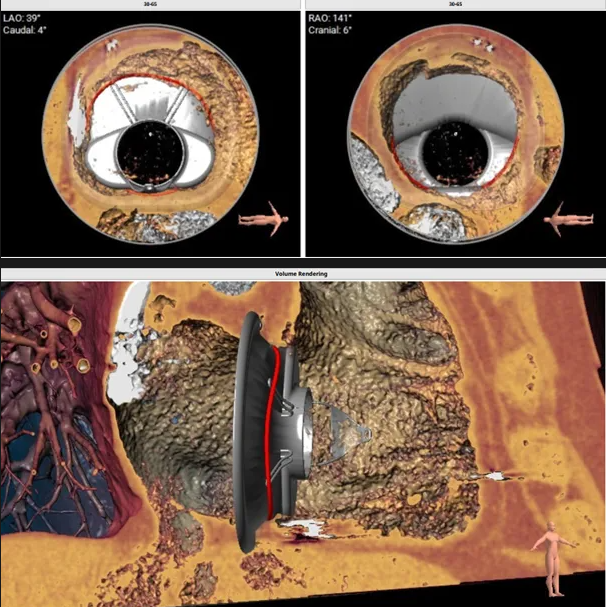

術(shù)前心臟CT評(píng)估

三尖瓣環(huán)平均周長(zhǎng)徑58.8mm,最大直徑62.2mm

三尖瓣環(huán)切線位夾角 85°

瓣膜植入模擬

術(shù)中經(jīng)食道超聲輔助下可見(jiàn)LuX-Valve Plus夾持件順利抓捕瓣葉,室間隔錨定位置良好,假體瓣膜整體錨定狀態(tài)穩(wěn)固。